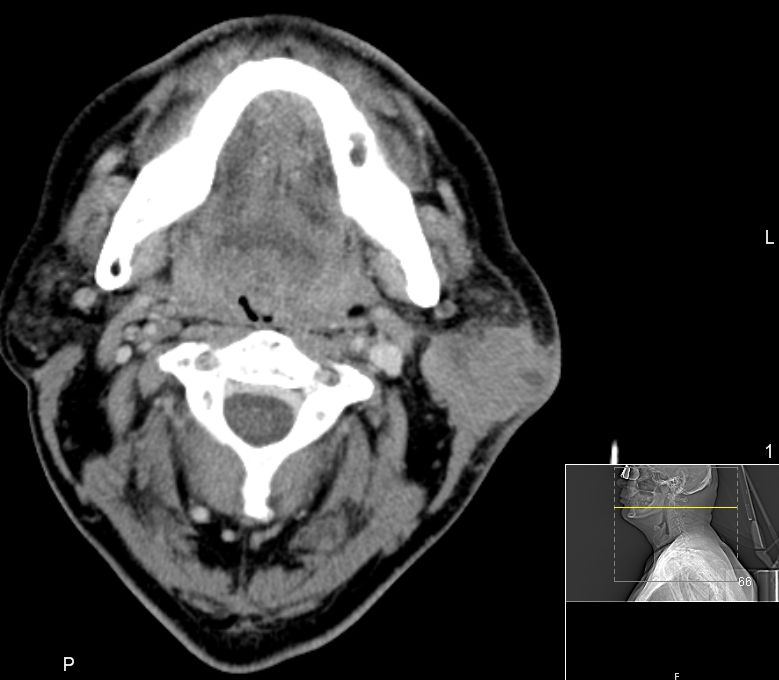

| CT | 51-jähriger Mann, der eine Gesichtsschwellung bemerkte. Adenokarzinom pT3 pN1 Mo L1 G3. Subtotale Protidektomie unter Neuromonitoring, ND LI und II links, Adjuvante RT. ![]() |